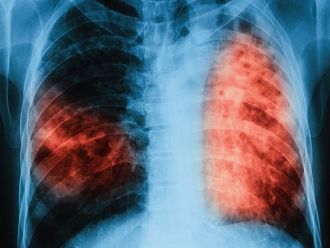

Характерно за латентната туберкулоза е, че тя преминава безсимптомно и при инфектираните лица не се наблюдават клинични, микробиологични или рентгенологични данни за наличие на активно туберкулозно заболяване. Макар че хората с латентна форма на заболяването не проявяват явни симптоми на активна туберкулоза и не са носители на заразата, те могат да бъдат окачествени като постоянни резервоари на инфекцията. При някои от тях има повишен риск от развитие на активно заболяване и те могат да станат източник на инфекция, обясни д-р Давчев.

Бързото диагностициране и адекватното лечение на болните с активна туберкулоза са от първостепенно значение за осъществяване на контрол над коварното заболяване. Също така трябва да се проследи и състоянието на лицата, които са били в контакт с болния от активна туберкулоза. Ранното откриване гарантира не само излекуване на вече заразените, но и прекъсване на веригата на предаване на болестта, подчерта д-р Веселин Давчев.